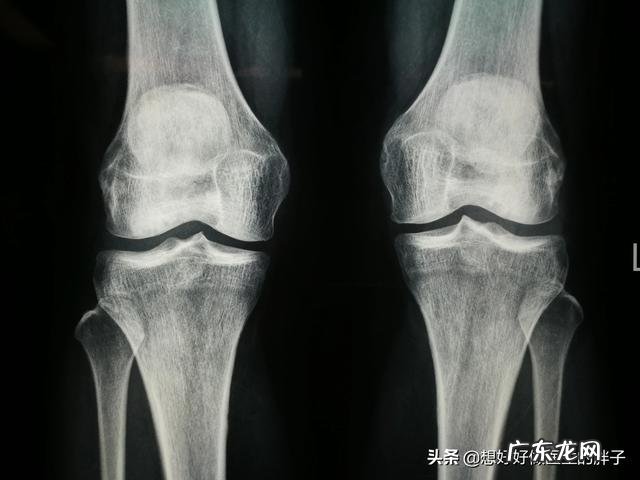

如果患者是由于骨关节炎导致的关节疼痛,那么建议可以到医院进行相应的检查,比较初步的检查有膝关节的x光片子,通过x光检查,我们可以明确患者是否有严重的骨赘形成,是否有关节间隙的狭窄,给予膝关节的病情做一个初步的判断 。

一般医生会根据x光以及膝关节核磁的检查,来判断患者的病情是处于哪一个阶段 。